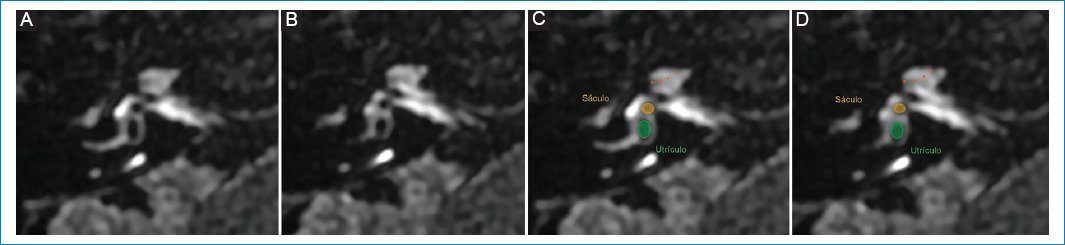

Varón de 52 años con acufenos pulsátiles en el oído derecho y vértigo episódico. No tomaba medicación. La RM mostró hallazgos coincidentes con hidrops vestibular de grado I (Fig. 5).

Figura 5. (A y B) Hidrops vestibular de grado I: dilatación del sáculo, vistas de superior a inferior; representación esquemática en C y D.

Varón de 59 años que concurrió a la guardia por vértigo de más de un mes de evolución, hipoacusia del oído derecho, sensación de oído tapado y zumbidos aislados. Los síntomas habían aumentado de frecuencia en los últimos días. La RM evidenció hallazgos compatibles con hidrops vestibular de grado II (Fig. 6).

Figura 6. Hidrops vestibular de grado II: dilatación del sáculo y del utrículo con confluencia de ambos, persistiendo un fino realce perilinfático periférico, (A y B) vistas de superior a inferior; representación esquemática en C y D.

Paciente 5

Mujer de 49 años que presenta hipoacusia en el oído derecho y crisis de vértigo de cinco años de evolución, que se fueron incrementando en frecuencia. La RM con protocolo de hidrops mostró borramiento total de las estructuras vestibulares, tal como se describe en pacientes con hidrops vestibular de grado III (Fig. 7).

Figura 7. (A y B) Hidrops vestibular de grado III: dilatación del sáculo y del utrículo, con confluencia de ambos, y pérdida del reborde perilinfático, vistas de superior a inferior; representación esquemática en C y D.